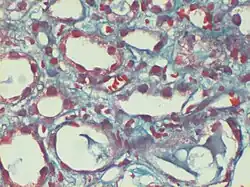

Gömöri trichrome stain

Gömöri trichrome stain is a histological stain used on muscle tissue.[2][3]

It can be used to test for certain forms of mitochondrial myopathy.